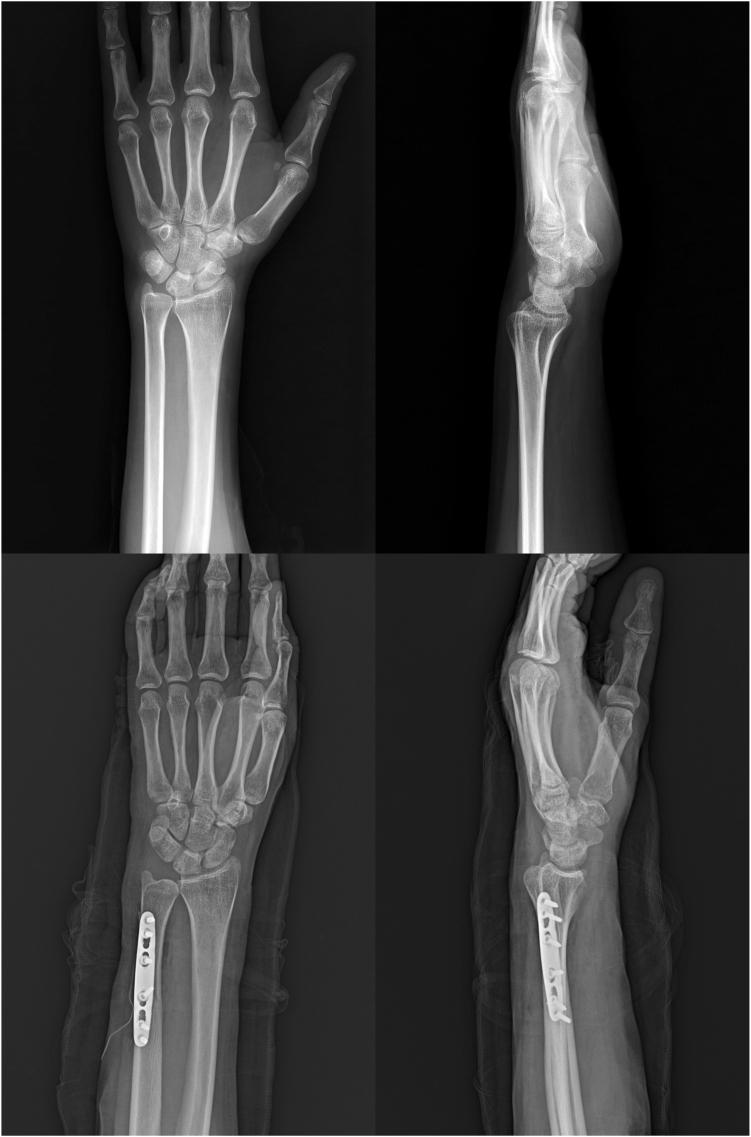

Chylous joint effusion is a rare condition characterized by the presence of a milky, viscous synovial fluid with abnormal lipid concentrations. The thorax is the most common site of involvement. Only a handful of cases have been reported in the field of orthopedic surgery and even fewer have been reported involving uncommon locations such as the knee. Treatment of chylous joint effusion may require surgical intervention along with the use of somatostatin or octreotide and a low-fat diet. We present herein a case of post-traumatic chylous effusion in the wrist treated with surgical incision and drainage, octreotide, and a low-fat diet. There have been few reports of chylous effusion in the knee; however, to our knowledge, this is the first report of post-traumatic chylous effusion in the wrist.

https://cdn.ncbi.nlm.nih.gov/pmc/blobs/5da5/11133889/a565136bdae1/gr1.jpg